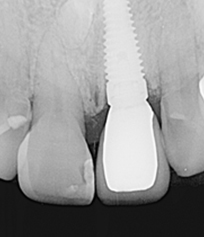

半年後假牙完成全口X光片、口內正面照片。

假牙完成X光片。